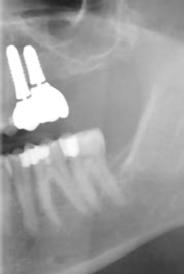

3. a–b ábra: Röntgenfelvételek három hónap után (a) és a gyógyulási csavarok behelyezve (b, 1. eset).

4. a–b ábra: Röntgenfelvételek öt hónappal később (a) és a gyógyulási csavarok behelyezve (b, 2. eset).

5. a–c ábra: Röntgenfelvételek öt hónappal később (a) és a gyógyulási csavarok behelyezve (b és c, 3. eset).

6. a–b ábra: Röntgenfelvételek öt hónappal később (a) és a gyógyulási csavarok behelyezve (b, 4. eset).